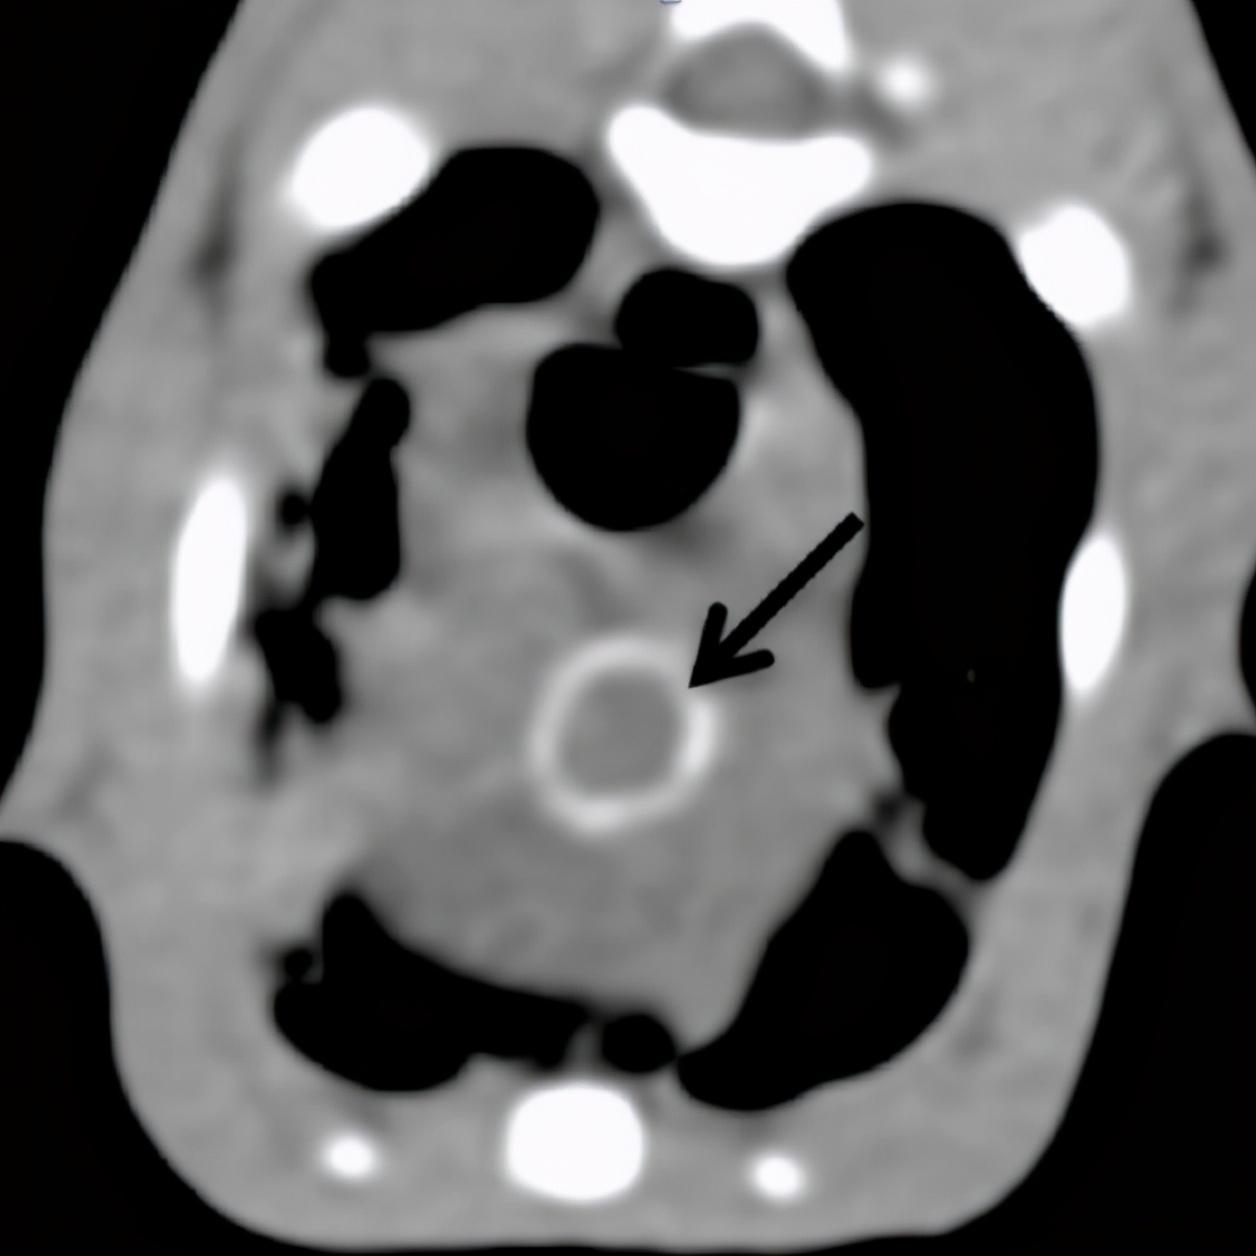

疱疹病毒等检测隐形,抗生素治疗不敏感,血液检查发现高钙血症,CT显示主动脉弓、主动脉根部矿化,肺部表现与矿化、纤维化或炎症表现一致。

经详细病史排查及第三方机构检测,发现主人饲喂的罐装零食存在维生素过量,诊断为高维生素D中毒。